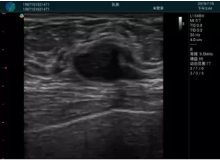

清晰顯示腺體內(nèi)低回聲快影,邊界清晰,包膜較光滑

確定進(jìn)針路徑并實(shí)時(shí)監(jiān)測(cè)抽吸針與腫塊位置關(guān)系

抽吸針進(jìn)入腫塊內(nèi)部進(jìn)行旋切

抽吸過程中可見腫塊明顯縮小,并根據(jù)腫塊位置改變針道位置

抽吸旋切后再進(jìn)行超聲復(fù)查,原腫塊區(qū)域未見殘留組織及出血